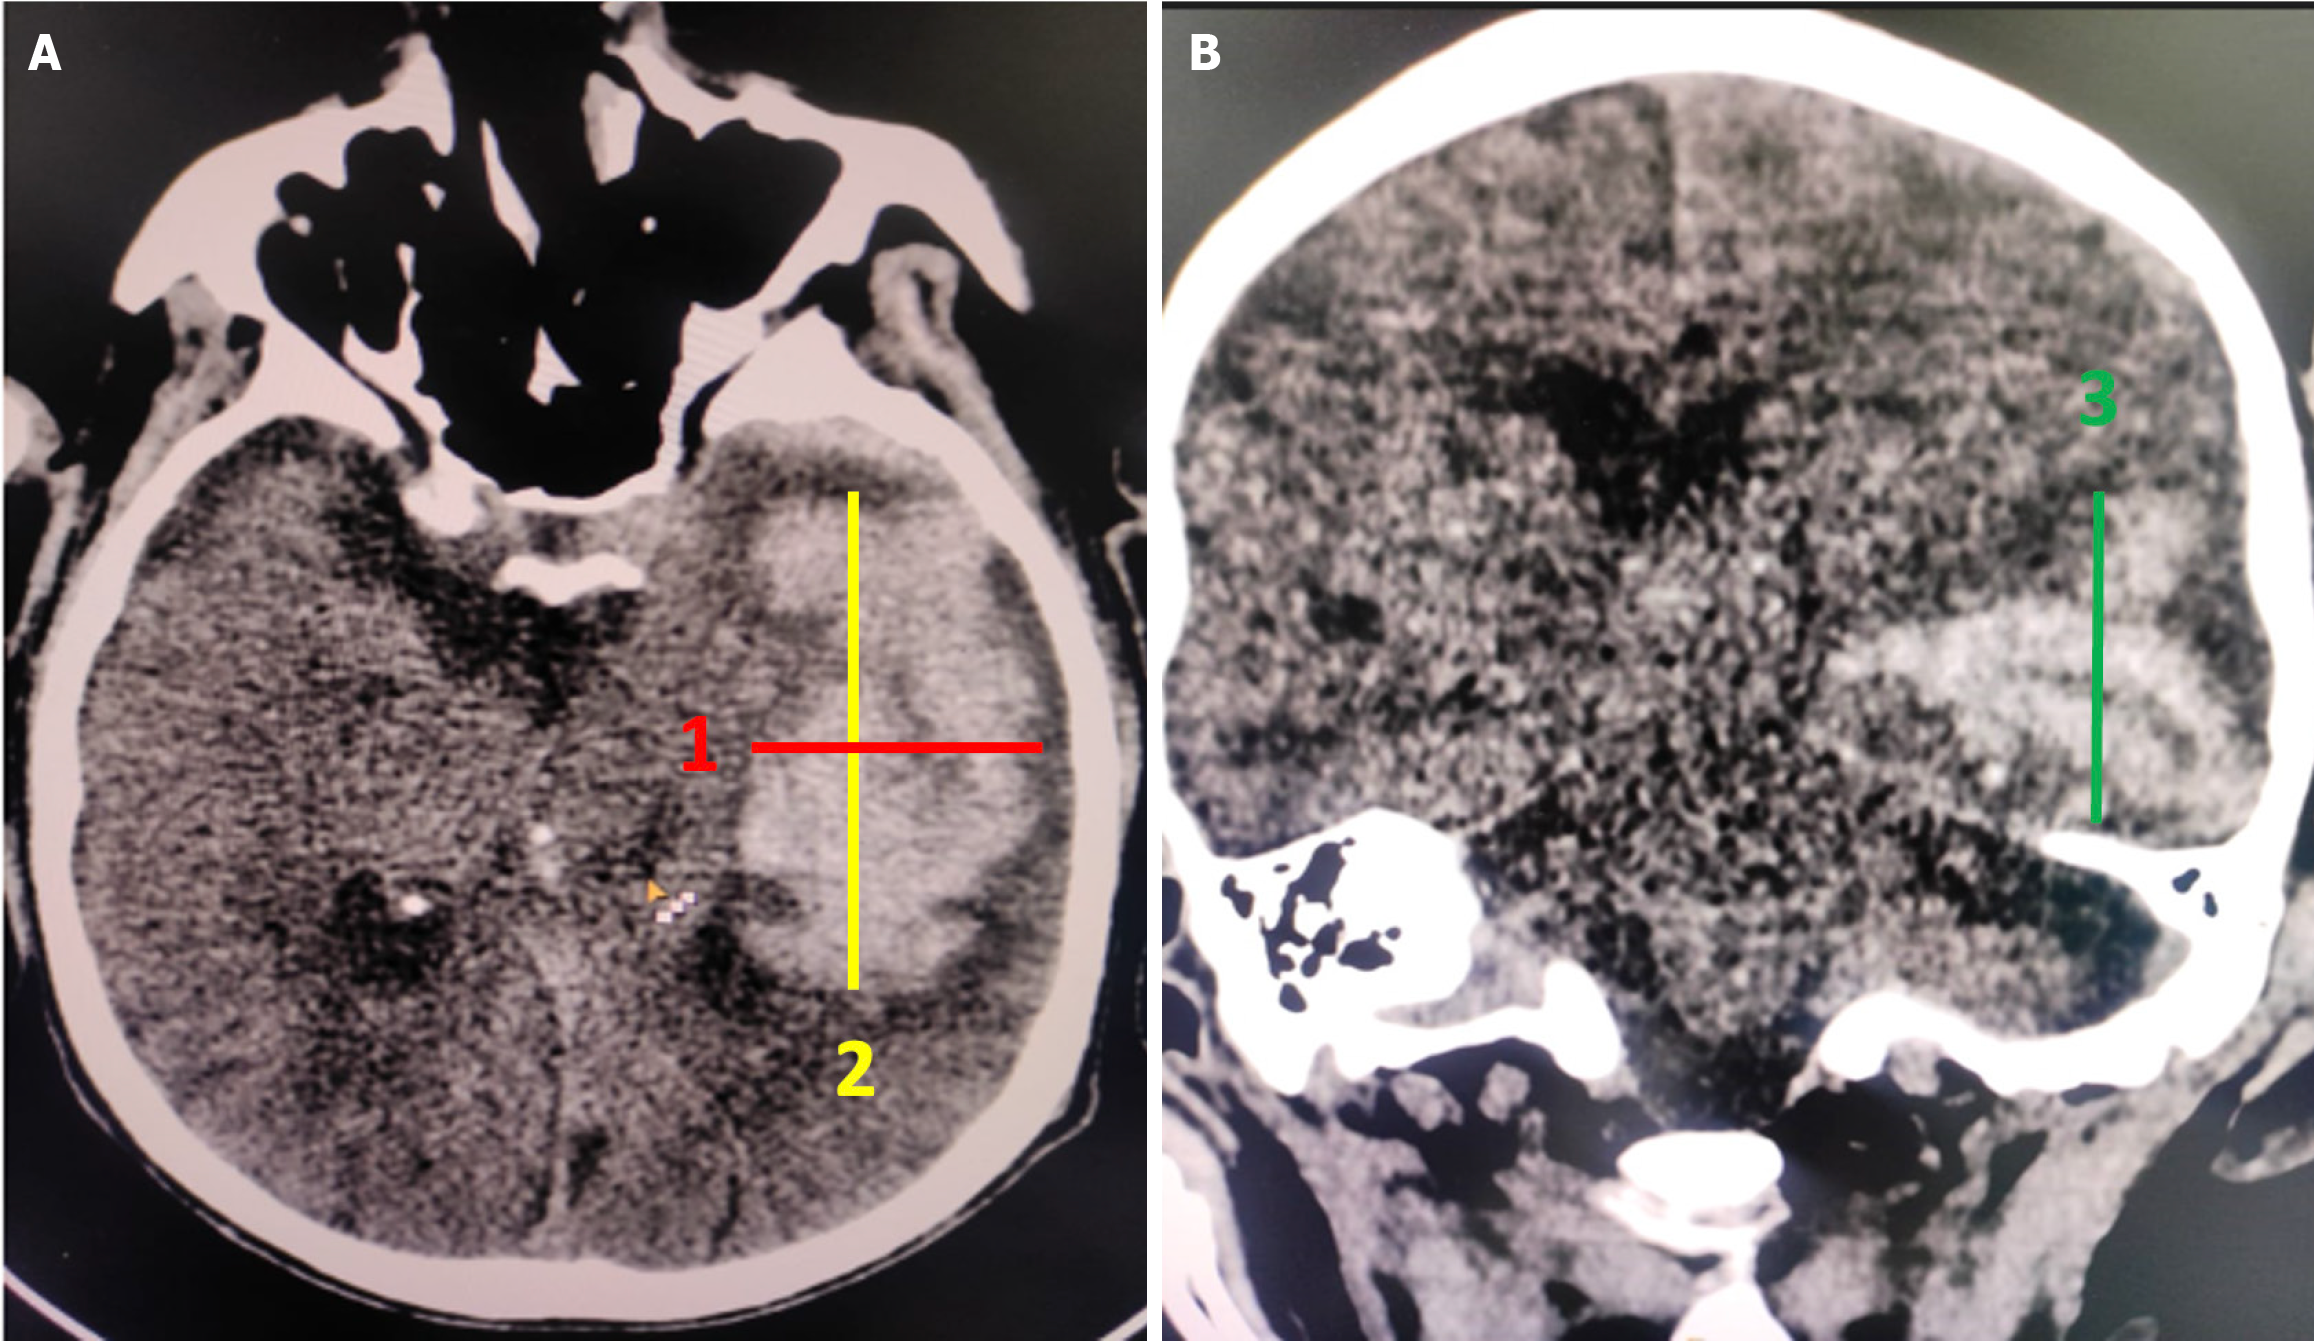

The volume of the hematoma was measured using the simplified ellipsoid formula, ABC/2[11]. First, the CT slice showing the largest hematoma size was selected. The longest dimension of the hematoma on this slice was measured as in Figure 2A, and then the dimension perpendicular to it was measured as in Figure 2A. The third measurement was acquired either by multiplying the number of slices containing the hematoma by the slice thickness or by measuring the craniocaudal dimension (as in Figure 2B) in the coronal plane (Figure 2).